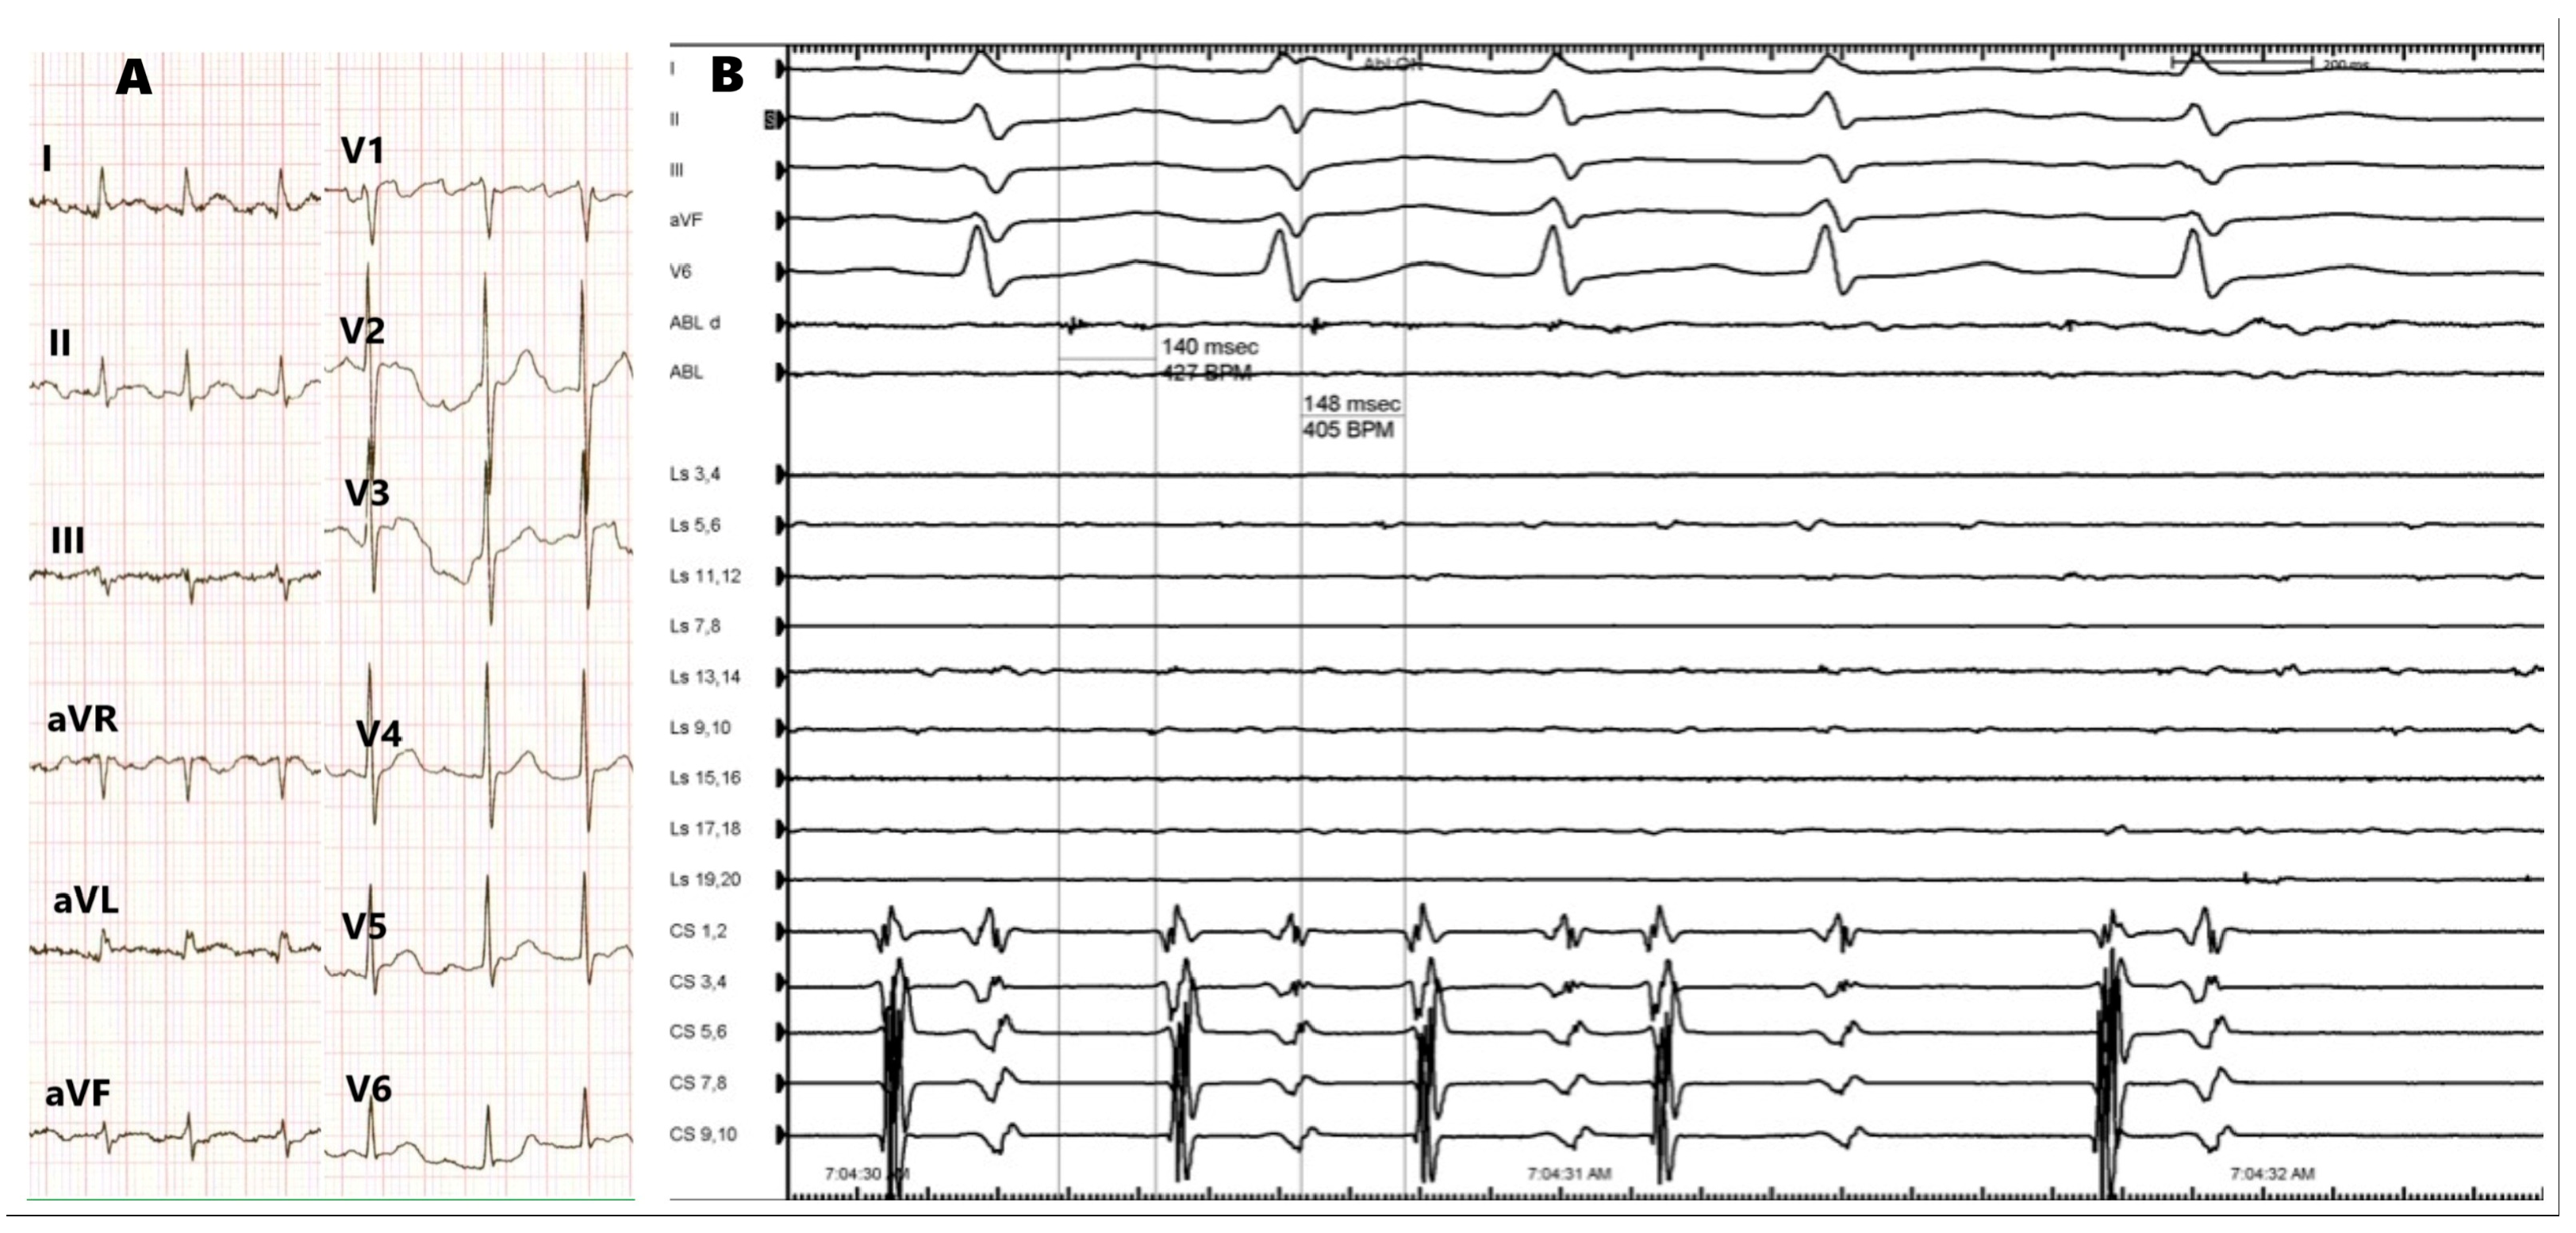

2. Case Presentation